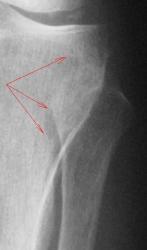

Конечно, можно предположить, что повреждающий фактор (альтерация) действовал, как показано стрелками, т.е. первопричиной все-таки была какая-то травма (надо объяснить контактность поражения). А можт быть это не остеохондропатия?

4. При анализе проксимального эпи-метафиза б/берцовой кости, локальные участки остеопороза, отмеченные стрелками, связаны, по всей видимости, именно с функциональной недостаточностью мениска и связки, а также с наличием феморо-пателлярного артроза, что функционально выразилось в "недогрузе" латеральных отделов коленного сустава, (возможно даже из-за болевого синдрома, не исключается "подсознательная разгрузка"), и переносе "нагрузки на медиальные отделы.

Имеет место частичное окостенение (на фоне суставной щели) латерально связочно-сумочных компонентов (по С.А. Рейнбергу), но по всей видимости - локальные окостенения латерального мениска. Создается впечатление, что головка м/берцовой кости, как "контрразведка" закрывает зону остеопороза (локального), о нем также свидетельствует локальная "подчеркнутость" на данном месте "кортикала".